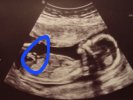

Chlopiec czy dziewczynka ?

Moja dzidzia wczoraj miała właśnie taki wyrostek który na końcu się rozdzielał.

Nie mam pewności czy to wyrostek a może peopowina 😅

Masz na myśli tą część z 2 kreskami co wystaje w lewą stronę do góry? To wg mnie kości nogi. Jakby się przyjrzeć, to za jest druga nóżka.

na pewno nie noga bo u mojej dzidzi tak to wyglądało między nogami I początkowo myślałam że chlopiec ale uważam że to coś było za długie i dziwnie rozdzielalo się na boki przy końcu